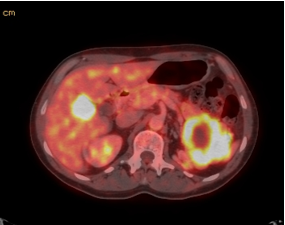

A computed tomography and positron emission tomography (CT/PET) scan was performed for staging and revealed a large 7.5 by 10 cm mass in the left upper quadrant of the abdomen that had a necrotic center and involved several loops of small bowel (Figure 2).

Figure 2 CT/PET scan showing liver nodule and large left upper quadrant mass with necrotic center.

In addition, the patient had liver nodules, and right lower quadrant abdominal lesions. The patient was seen by oncology and started on Imatinib. Four months after initial diagnoses, a repeat CT/PET scan revealed a decrease in the volume of his disease. He was continued on Imatinib therapy; however, he developed resistance which was evident with tumor growth. He was subsequently switched to Sunitinib therapy, but he was noted to have continued growth and deemed nonresponsive. He was taken to the operating room for tumor cytoreduction 32 months after diagnosis. Heunder went en bloc resection of the left upper quadrant mass involving the splenic flexure of the colon and jejunum with primary jejunal anastomosis. He had tumor nodules involving the right colon, and therefore an extended right hemicolectomy with ileosigmoid anastomosis was performed. He also required resection of segment V of his liver for 3 metastatic nodules. The left upper quadrant tumor on final pathology was 9.5 cm, and the nodules in the right colon and liver were metastatic nodules. He had 2 out of 8 lymph nodes positive. He was then treated with Regorafenib, and will be followed with CT/PET scans.